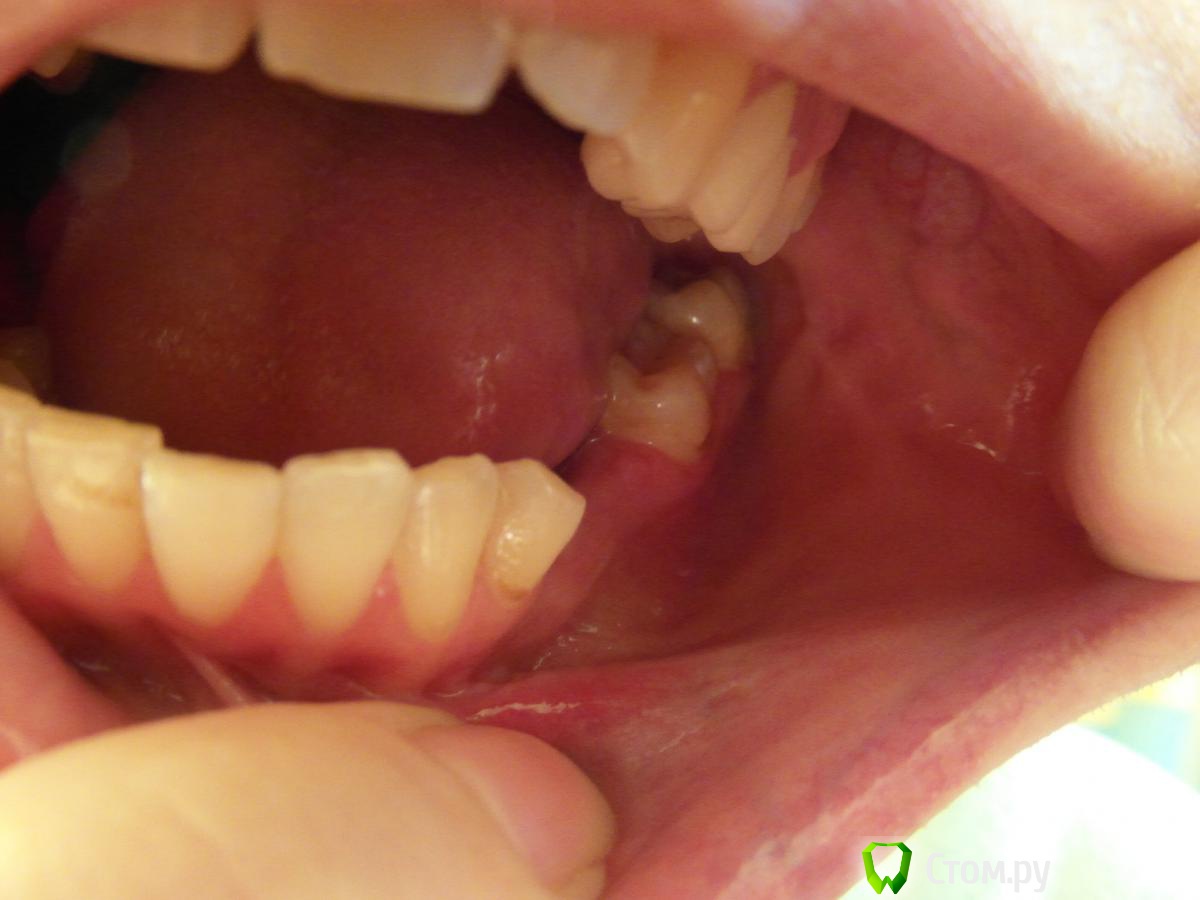

Ланская Опубликовано 11 июня, 2014 Поделиться Опубликовано 11 июня, 2014 После неудачного операционного вмешательства разрез зажил вторичным натяжением,рубцовые изменения многих тканей по переходной складке в области 35-37 зубов..В Питере не могу найти ни одного врача по лечению рубцовой ткани. Подскажите,пожалуйста,как можно размягчить рубцовую ткань?Боли и стягивание не выносимые,трудно делать мимические движения,кушать.Спрашивала у врачей про стекловидное тело и букки-терапию,но они про это и не слышали.Не знаю можно ли проводить физиотерапию с лидазой?Так как в десне вместе срастания не понятное уплотнение и не заживающая язвочка.После операции прошло семь месяцев. Ссылка на комментарий

Ланская Опубликовано 11 июня, 2014 Автор Поделиться Опубликовано 11 июня, 2014 Здравствуйте! Спасибо врачам,которые откликнулись.Рубец сфотографировать было сложно,надеюсь хоть что-то будет видно на снимке. Ссылка на комментарий